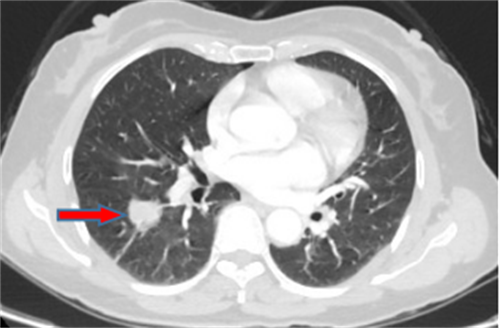

王女士,57岁,体检发现右下肺结节2月,术后病理诊断肺结节为肺隐球菌病。

李先生,45岁,发现右上肺结节2年,近期长大,术后病理诊断肺结节为炎性假瘤。

龙先生,65岁,体检发现右下肺结节,术后病理诊断肺结节为硬化性血管瘤。

郭女士,63岁,体检发现右下肺结节20天,术后病理诊断肺结节为浸润性腺癌。

王女士,65岁,体检发现右上肺磨玻璃结节16天,术后病理诊断肺结节为浸润性腺癌。

王女士,52岁,体检发现右上肺磨玻璃结节7月,术后病理诊断肺结节为原位腺癌。

王女士,35岁,新冠核酸检查阳性7天,胸部CT检查左上肺磨玻璃影,考虑新冠病毒性肺炎。